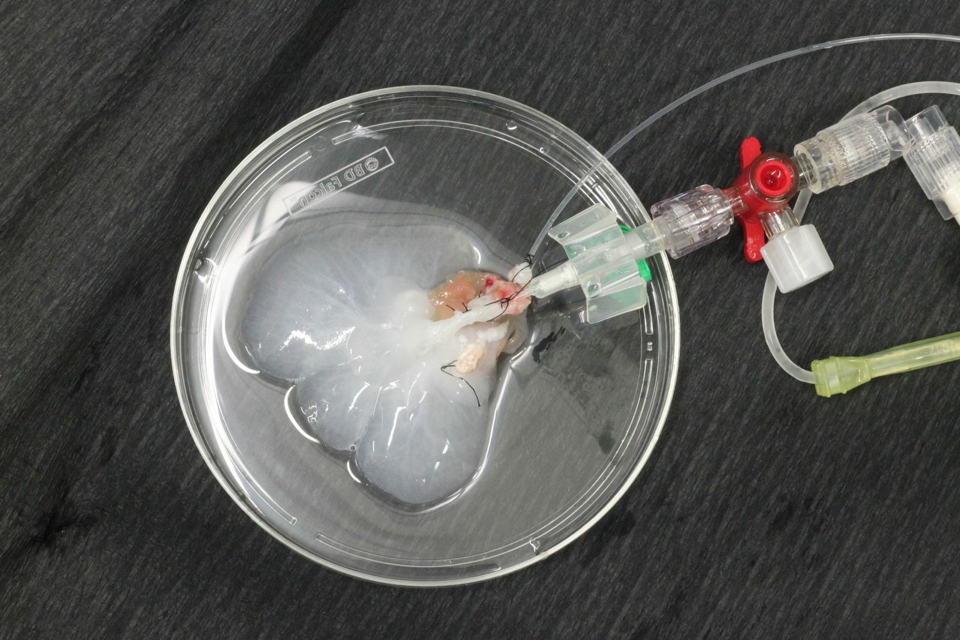

Recent reports on liver de- and recellularization provide evidence that the perfusion of alkaline detergents and/or enzymatic solutions via the portal vein is feasible to obtain a three-dimensional non-immunogenic biomatrix, that supports and improves survival and functionality of liver and/or progenitor cells. To enhance engraftment, migration and proliferation as well as to prevent dedifferentiation and loss of function of hepatocytes used for the repopulation of decellularized scaffolds, an adequate composition of micro-environmental conditions of the ECM is essential.

Since all known agents for liver decellularization cause alteration and damage to the ECM, a ‘gentler’ decellularization method may provide optimal support for cellular repopulation. On the other hand, ineffective decellularization leading to cellular and antigenic remnants within the ECM of allogenic or xenogenic origin could cause deleterious immunogenic effects (i.e., rejection) after implantation in vivo. Thus, finding an optimal compromise between cellular removal and preservation of the ECM composition (i.e., invasiveness of decellularization) should be addressed in further investigations to provide standardized decellularization protocols for livers from different species.

We developed a novel decellularization technique by perfusing with Triton X-100 and SDS via the hepatic artery under oscillating pressure conditions in a proprietary decellularization device. This device is designed to generate pressure changes on the perfused organ by mimicking intraabdominal conditions. In situ, the liver is adherent to the diaphragm and ‘hangs’ in its copula; the liver is affected mechanically by movement of the diaphragm during respiration. Whereas exhaling leads to lower intraabdominal pressure and increased portal-venous flow, inhaling (or increasing the intraabdominal pressure) causes higher outflow via the hepatic veins into the vena cava. This mechanism leads to a physiological aspiration of portal venous blood during expiration and a ‘squeezing’ of venous blood during inspiration, which can be likened to a ‘sponge’ and results in optimal perfusion of the liver.

Perfusion via the hepatic artery improves decellularization outcomes of rat livers compared to ‘conventional’ portal venous perfusion. Applying oscillating pressure conditions on extracorporeally perfused rat livers further enhances microperfusion and thus the homogeneity of perfusion decellularization. Using this technique the invasiveness of applied methodology can be reduced, resulting in a gentle and quick (3h) decellularization protocol for rat livers.

We developed a protocol for fast and homogenous porcne liver decellularization by simultaneous, pressure-controlled perfusion of detergents (i.e., 1% Triton X-100 and 1% SDS) via the portal vein and the hepatic artery. Livers were perfused under oscillating pressure conditions to improve the homogeneity and increase the effectiveness of the decellularization process. The oscillating pressure was generated by a vane-type pump, which improves microperfusion within livers by mimicking intraabdominal conditions during respiration. In situ, the liver is located under the copula of the diaphragm and follows the movement of the diaphragm during respiration. Thus, due to the lowering of the diaphragm and the increase in the intraabdominal pressure during inspiration, the liver is squeezed to optimize outflow of blood into the liver veins. During expiration, the diaphragm elevates the liver, the intraabdominal pressure decreases, and the inflow of portal venous blood into the liver is subsequently increased 20.